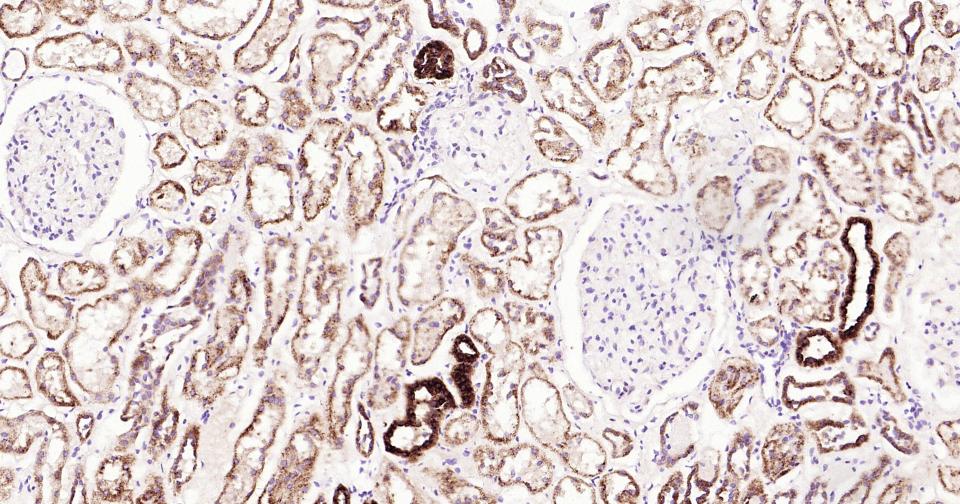

Paraformaldehyde-fixed, paraffin embedded Human Kidney; Antigen retrieval by boiling in sodium citrate buffer (pH6.0) for 15 min; Antibody incubation with Osteopontin? Monoclonal Antibody, Unconjugated(bsm-43600R) at 1:200 overnight at 4°C, followed by conjugation to the SP Kit (Rabbit, SP-0023)and DAB (C-0010) staining.